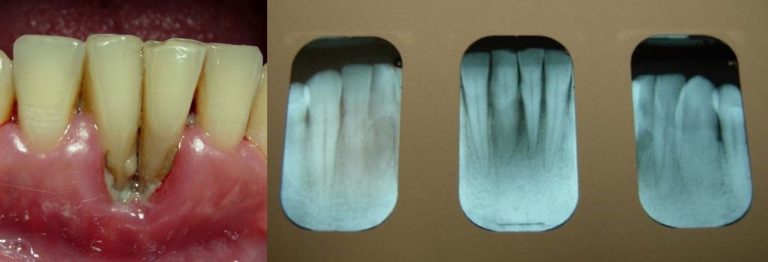

About half of the U.S. population >30 years of age is affected by chronic periodontal disease, and the prevalence of periodontal disease increases with age Eke, et al. 2015. No data currently exist to indicate the extent to which HIV infection may accelerate the destruction of periodontal tissues in the population with HIV. However, the occurrence of rapid attachment loss may indicate severe immunosuppression Ryder, et al. 2012; Mealey 1996. Pre-existing periodontal disease can be diagnosed by clinical characteristics and radiographic examination for bone loss as recommended by the American Academy of Periodontology American Academy of Periodontology 2000; Armitage 1999. The clinical characteristics for chronic periodontitis include the presence of periodontal pockets, clinical attachment loss, and bleeding on probing. Radiographic analysis can reveal the presence of periodontal bone loss with horizontal or vertical bony defects. Increased mobility of teeth may also be observed in association with clinical attachment loss and bone loss.

Appendix: Photo- and Radiographs of Periodontal Disease Associated With HIV

Photographs courtesy of Dr. Gwen Cohen Brown and the Dental Hygiene Department of New York City College of Technology

Figure 1: Patient with linear gingival erythema (LGE)

Figure 2: Patient with necrotizing ulcerative periodontitis (NUP)

Figure 3: Patient with linear gingival erythema (LGE) and necrotizing ulcerative periodontitis (NUP)

Figure 4: Patient with necrotizing ulcerative gingivitis (NUG)

Figure 5: Patient with localized bone loss